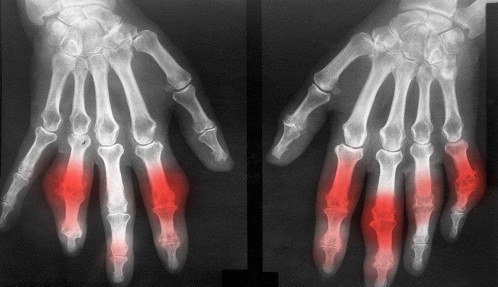

风湿性关节炎

类风湿

类风湿关节炎是一种全身性的疾病,出现了这...